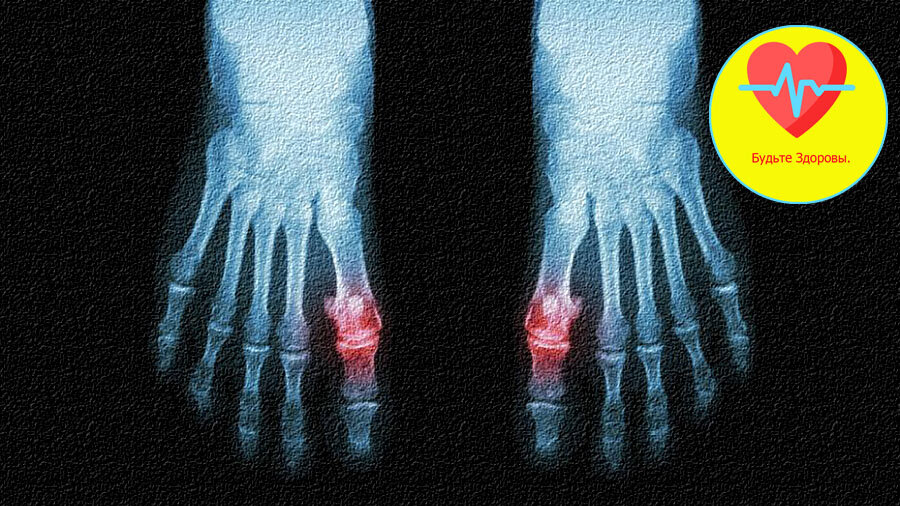

Подагра правых пальцев ног.

Подагра вызывает нарушение метаболизма, при котором страдают многие органы, но больше всего почки и суставы. Это более выраженное проявление артрита.

Чаще всего подагра наблюдается у мужчин в возрасте от 43-47, а у женщин после 50, но у женщин она встречается намного реже.